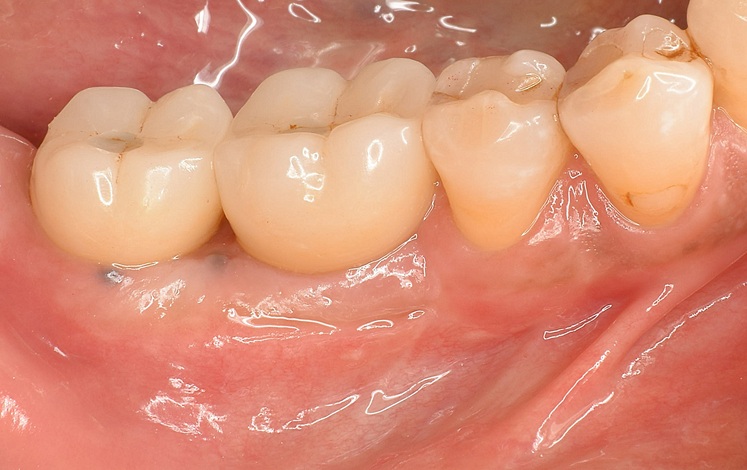

Case5

術前

術後

| 治療名 | サイナスリフトを併用したインプラントブリッジ症例 |

| 治療説明 |

奥歯に入っていたブリッジの支台歯にむし歯が見つかり、やむを得ず抜歯となりました。結果として奥歯が3本分欠損したため、患者さんとの相談のうえ、インプラントによる治療を選択しました。 |

| 治療回数・期間 | 約9ヶ月 |

| 副作用とリスク | ・入れ歯や従来のブリッジと比べ、治療期間が長くなる場合があります。 ・骨造成(GBRやサイナスリフト)を伴う場合、さらに治療期間が延びることがあります。 ・インプラント手術後には、一時的に違和感、痛み、腫れ、出血が生じることがありますが、通常は2日〜1週間で落ち着きます。 ・サイナスリフトは、まれに上顎洞への感染リスクがあるため、術後の経過観察が重要です。 |

| 料金(税込) | 小規模GBR:110,000円 サイナスリフト:220,000円 インプラント一次手術×2本:440,000円 二次手術×2本:110,000円 上部構造〈インプラントブリッジ〉:495,000円 合計:1,375,000円 |